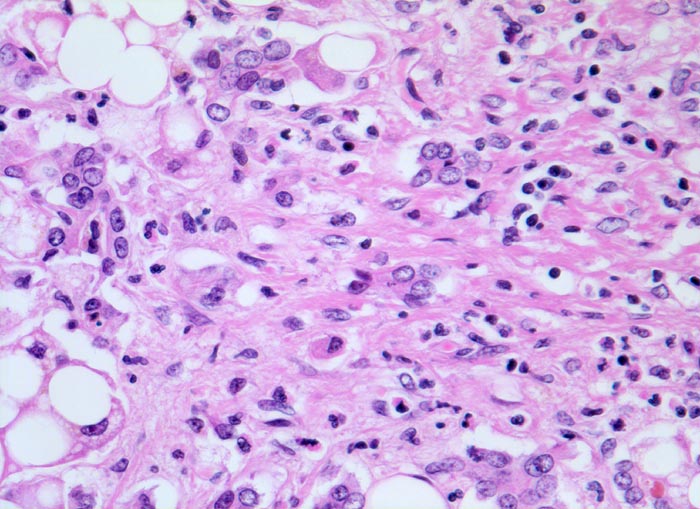

• Floride sklerosierende alkoholische Steatohepatitis: Grobtropfige Verfettung von ca. 50% des Parenchyms.Neutrophile Granulozyten umgeben einzelne Hepatozyten (Satellitose). Wenig Apoptosekörperchen. Zahlreiche Mallory Körperchen und Megamitochondrien. Perivenuläre Maschendrahtfibrose.

• Hydropische Schwellung periportaler Hepatozyten.

• Canaliculäre Cholestase in einem Zirrhoseknoten.